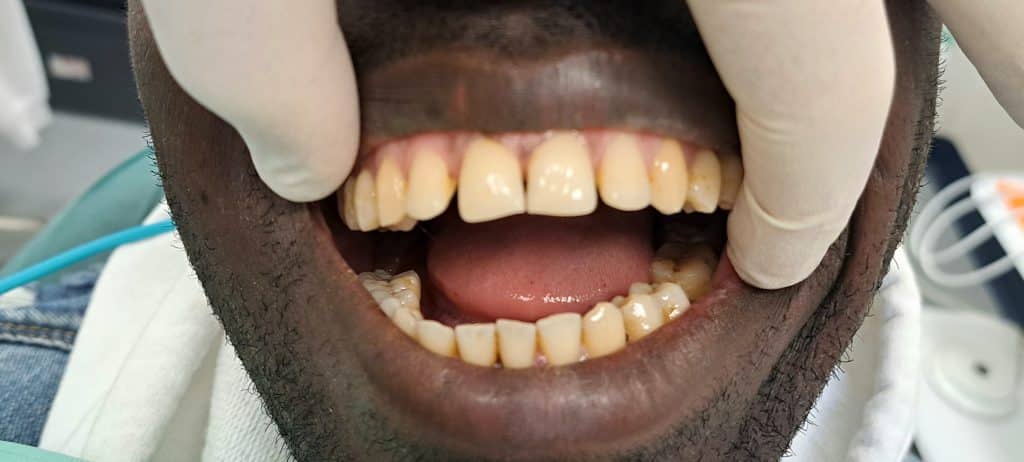

All’esame clinico, si evince mobilità del 3.8 gravemente compromesso e la ridotta apertura della bocca.

Vista la ridotta apertura della bocca e quindi l’impossibilità ad utilizzare la pinza per estrarre il molare, la scelta ricade su estrazione con sola leva.

Dopo aver effettuato anestesia tronculare in metodica diretta, si prosegue con l’estrazione dell’elemento avvenuta con successo.